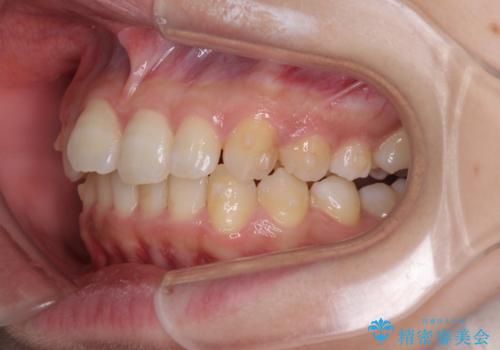

- 前歯のデコボコと奥歯の不正咬合を気にして来院された患者様です。

左右の大臼歯が全て鋏状咬合(シザーズバイト)になっており、治療が難航することが予想されましたが、インビザラインにより治療を行うこととしました。